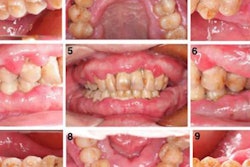

A clinical exam revealed generalized gingival enlargement. Also, her gums were inflamed, and there was visible plaque. During periodontal probing, she experienced extreme sensitivity and profuse bleeding in response to probing. The woman was diagnosed with generalized gingivitis and drug-influenced gingival enlargement.

Initially, the patient underwent supra- and subgingival debridement of the affected area, as well as prophylaxis to eliminate plaque and calculus. She was given oral hygiene instructions and a prescription of 0.12% chlorhexidine antimicrobial mouthrinse to aid in plaque control, the authors wrote.

At a reevaluation one week later, the tissues remained erythematous and enlarged. She also reported that her symptoms remained the same. A month after the initial consultation, she underwent a biopsy. The results confirmed a diagnosis of ulcerated inflammatory fibrous hyperplasia. This diagnosis was consistent with drug-influenced gingival enlargement, they wrote.

During two more monthly follow-up appointments, she had thorough debridement with minimal improvements. Due to negligible improvement and her declining the gingivectomy, her nephrologist agreed to reduce her dose of voclosporin.